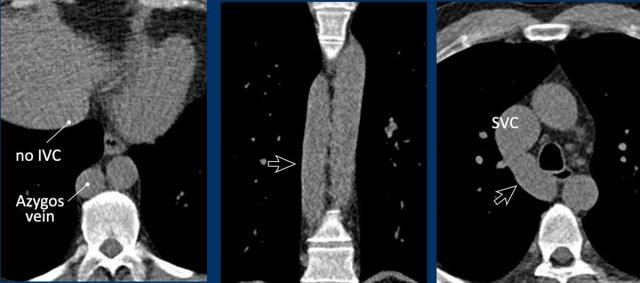

Tĩnh mạch chủ dưới tiếp nối qua tĩnh mạch đơn

Trong biến thể này, đoạn tĩnh mạch chủ dưới dưới gan bị thiếu, các đoạn dưới thận và ngang thận dẫn lưu qua tĩnh mạch đơn giãn lớn vào tĩnh mạch chủ trên.

Đoạn tĩnh mạch chủ dưới trên gan vẫn hiện diện nhưng chỉ dẫn lưu máu từ các tĩnh mạch gan vào tâm nhĩ phải.

Tĩnh mạch chủ dưới tiếp nối qua tĩnh mạch đơn thường là phát hiện tình cờ ở bệnh nhân không có triệu chứng, mặc dù có thể đi kèm với các bất thường tim mạch khác, cũng như với tình trạng không có lách hoặc đa lách.

Tầm quan trọng của việc không bỏ sót tình trạng này chủ yếu liên quan đến ý nghĩa trong lập kế hoạch phẫu thuật cũng như các thủ thuật nội mạch, vì nó cản trở việc đặt ống thông vào tim phải từ phía dưới.

Hình ảnh

Tĩnh mạch chủ dưới tiếp nối qua tĩnh mạch đơn cho thấy hình ảnh đặc trưng ‘động mạch chủ đôi’ ở mức trụ hoành, và sự giãn của tĩnh mạch đơn kéo dài đến điểm nối với tĩnh mạch chủ trên.